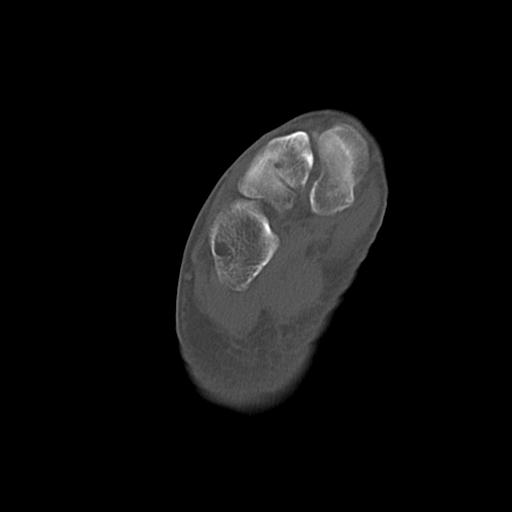

49554 3/13 膝 4R 3/16 4R 1/18 2R 78歳男性 膝蓋骨骨折